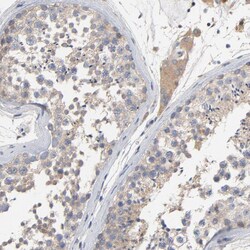

Invitrogen™ CCDC134 Polyclonal Antibody

The coiled-coil domain is a common protein motif that is often involved in protein oligomerization and is found in proteins such as transcription factors and intermediate filaments. One such protein is CCDC134, a recently identified secretory protein that has been found to inhibit the transcriptional activity of the Elk1 protein. Overexpression CCDC134 also inhibited the phosphorylation of Erk and JNK/SAPK but not p38 MAPK, while specific siRNA against CCDC134 activated Elk1 transcriptional activity and the phosphorylation of Erk and JNK/SAPK, suggesting a potential inhibiting role of CCDC134 in MAPK-mediated Elk1 transcription. CCDC134 is widely expressing in normal adult tissues, tumors, and cell lines.

| Applications | Immunohistochemistry (Paraffin), Western Blot |